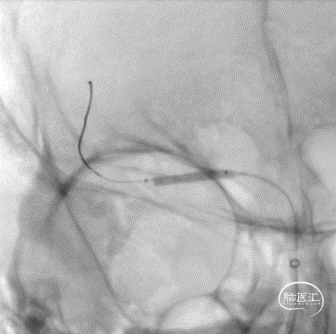

沿微导丝输送赛诺神畅 NOVA颅内药物球扩支架2.25*20mm支架到位,支架输送顺利,全过程无明显张力变化。

6atm缓慢扩张释放支架。

释放支架后造影见支架中段稍有残留狭窄,以8atm缓慢再扩张,残留狭窄消失。